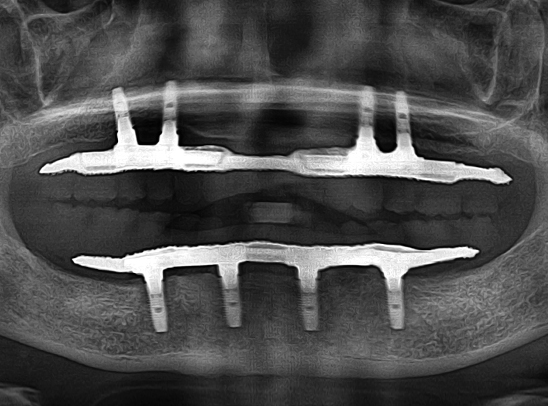

• 자체 기술로 제작한 치아몸통을 연결하여

임플란트를 4~6개만 식립 가능

식립 개수를 줄이는

시니올 임플란트

식립 개수를 줄인 시니올 임플란트

시니올 임플란트의 보철물은

기존 방식으로는 제작이 어렵습니다.

젊어지는치과에서는 시니올 보철물 제작에

특화된 전담 의료진이 보철물을 직접 디자인하고,

당일에 제작하여 끼워드립니다.

수술 후 임시 틀니를 착용하지 않기 때문에

틀니로 인한 고통이 없을 뿐 아니라

수술 당일부터 식사가 가능합니다.